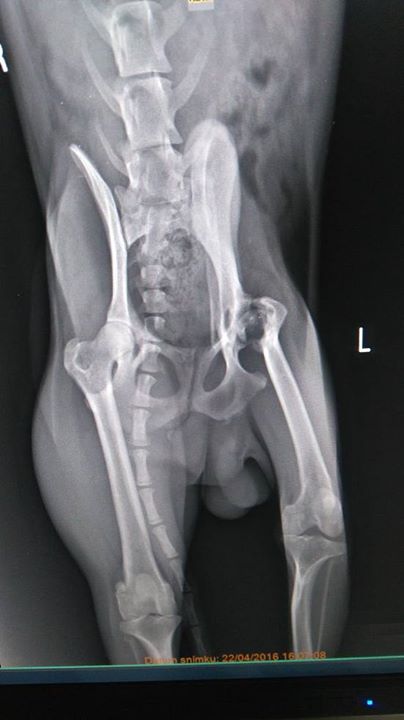

Amalka

Amalka na RTG vyšetrení. Amálka mala šťastie, neskončila v hrmci no jej zdravotné problémy po rôznych vyšetreniach a liečbe neustúpili. Jej deformovanie kostí sú trvalé, ktoré zrejme má od malička.